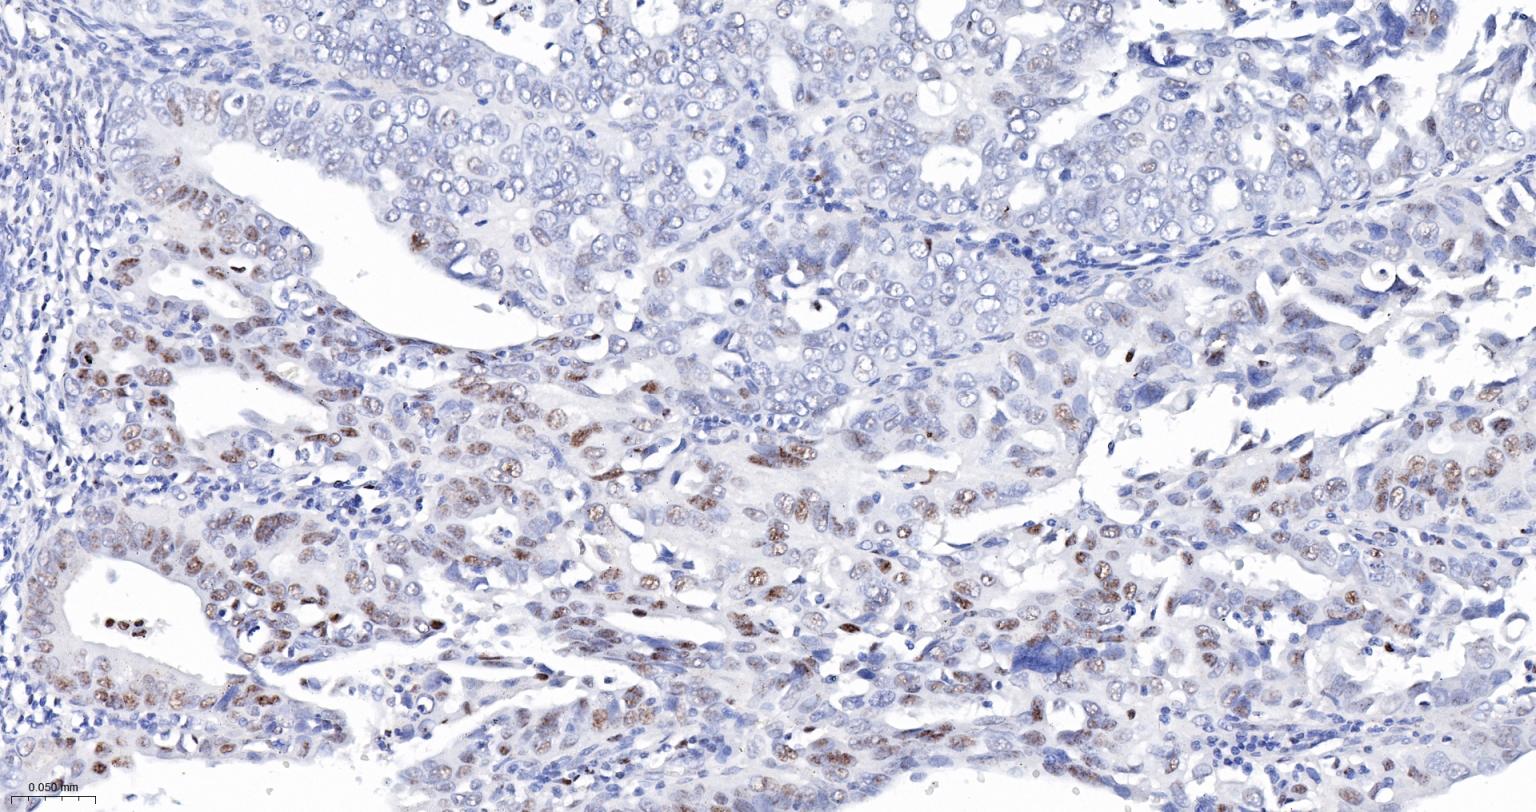

Paraformaldehyde-fixed, paraffin embedded Human Ovarian Cancer; Antigen retrieval by boiling in sodium citrate buffer (pH6.0) for 15 min; The section was incubated with PB1 Monoclonal Antibody, Unconjugated (bsm-61815R) at 1:200 overnight at 4°C, followed by conjugation to the bs-0295G-HRP and DAB (C-0010) staining.